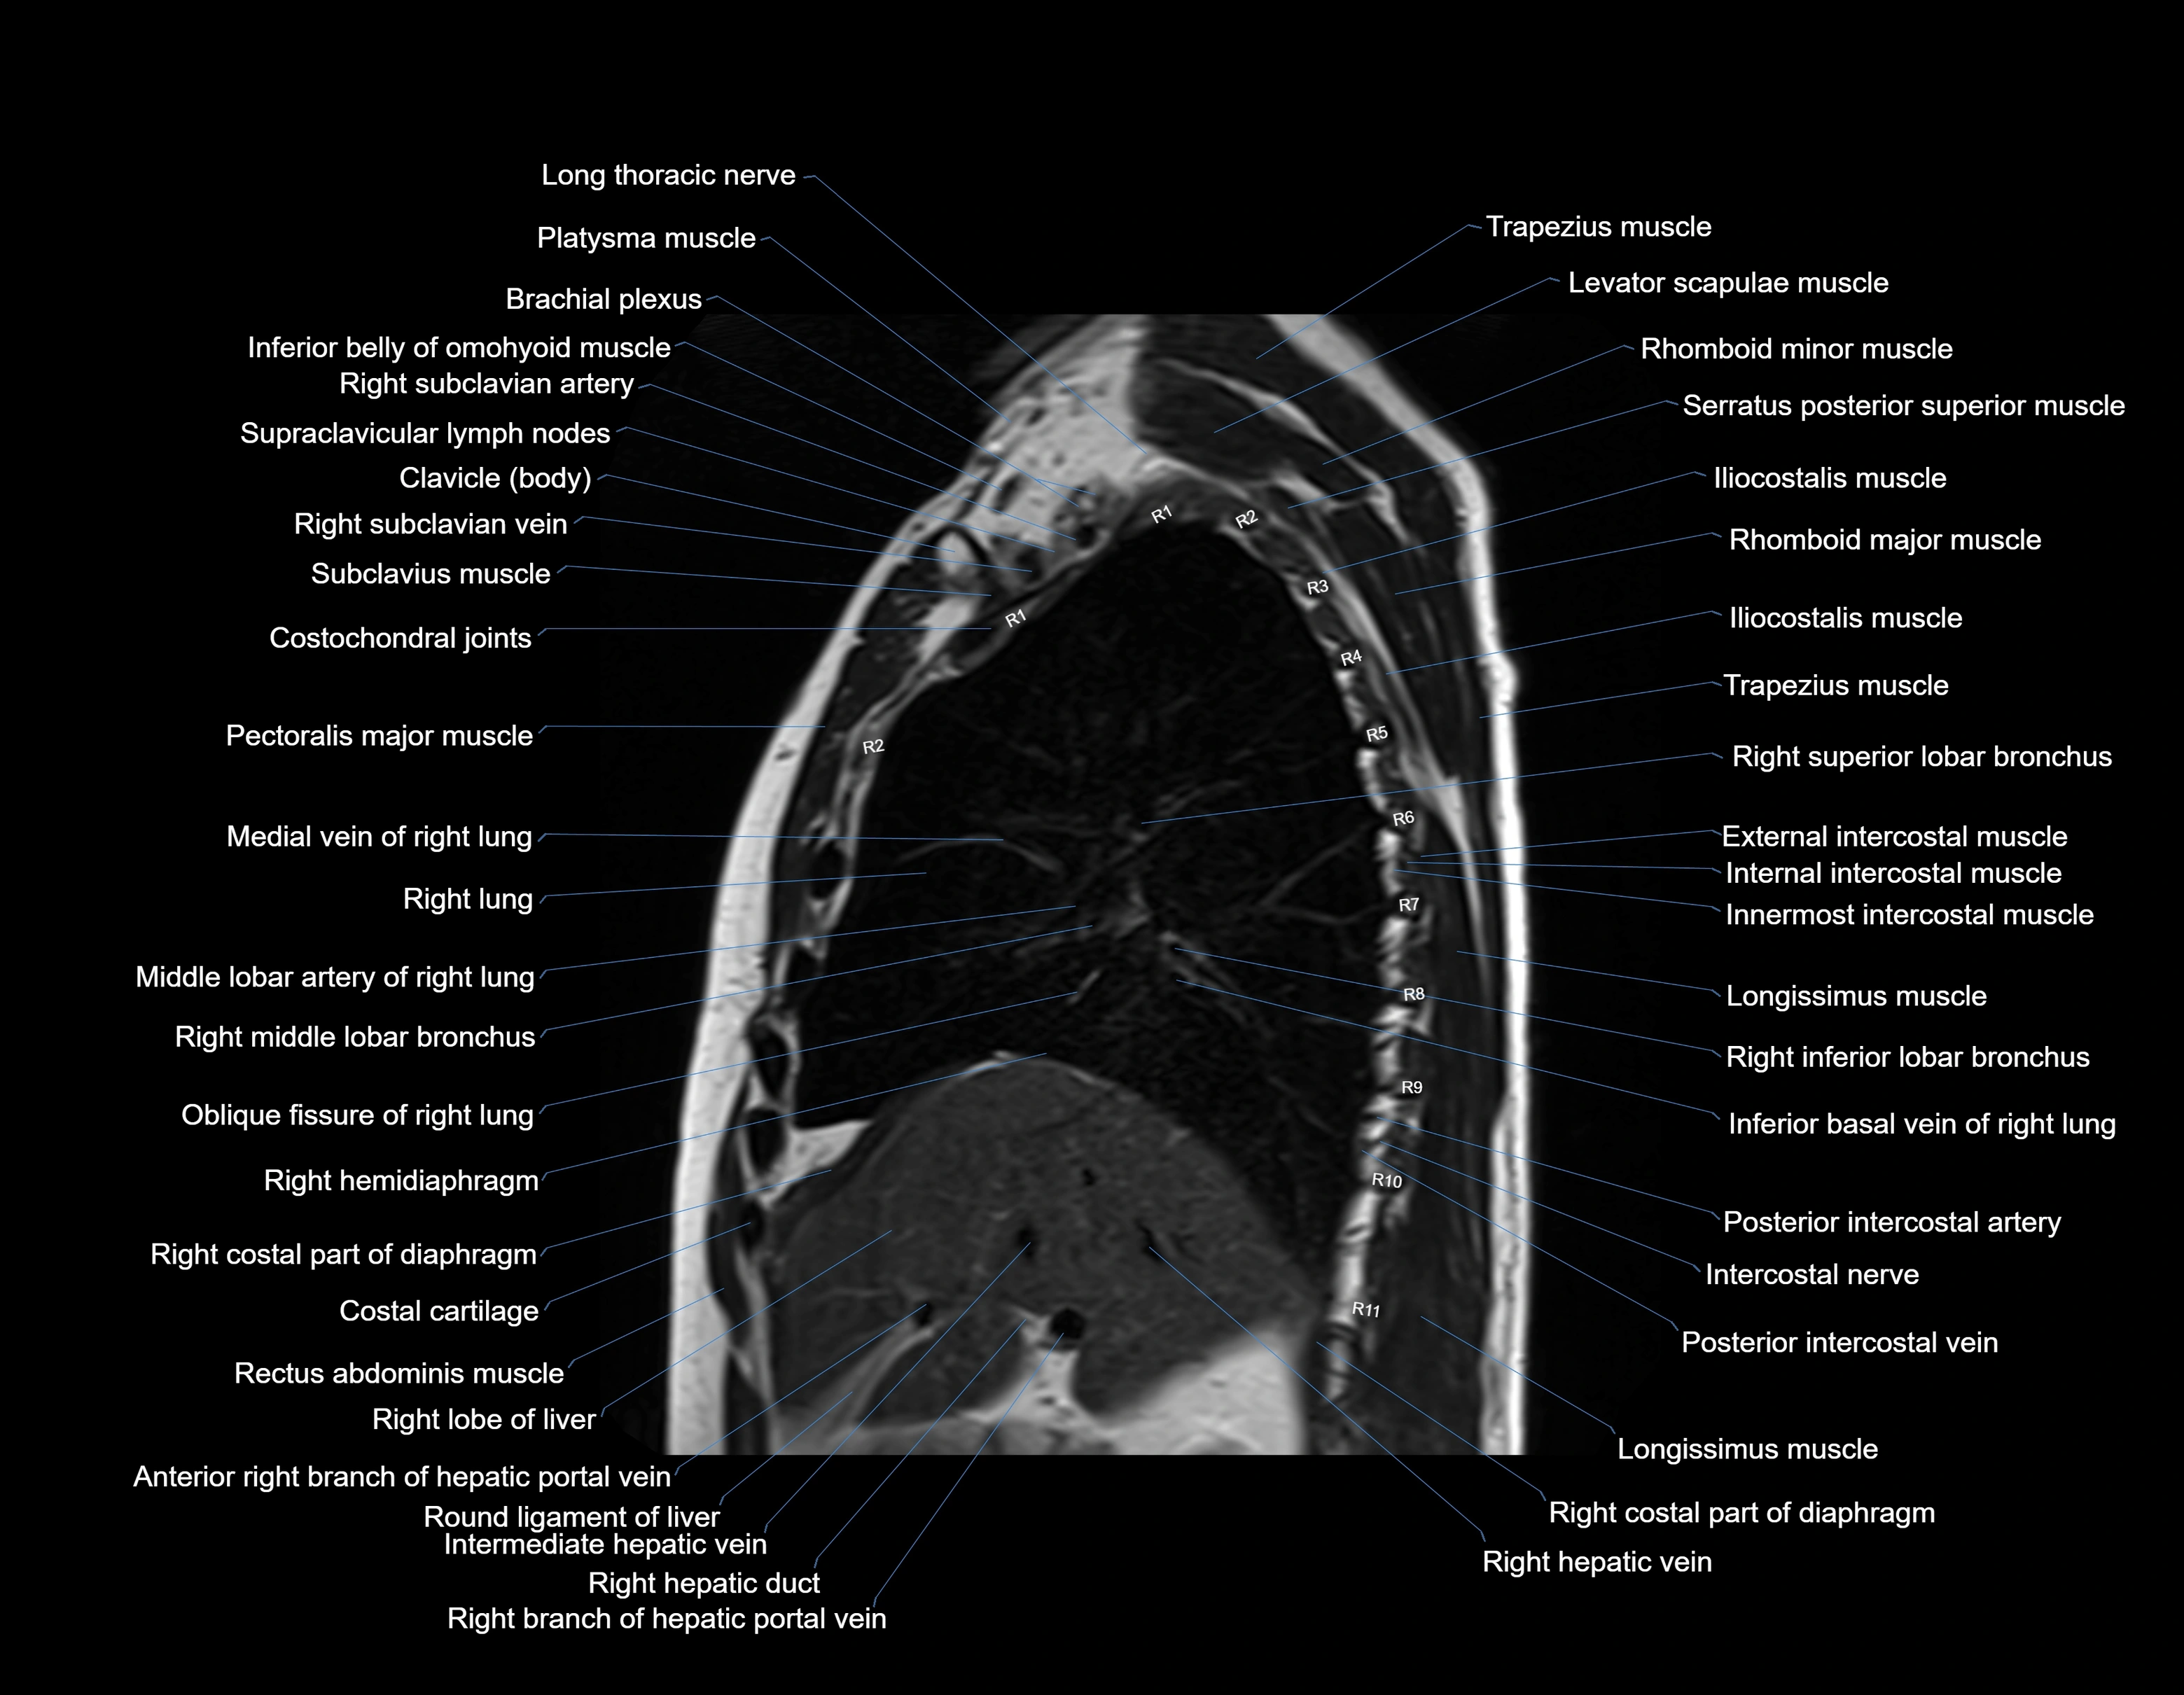

MRI images